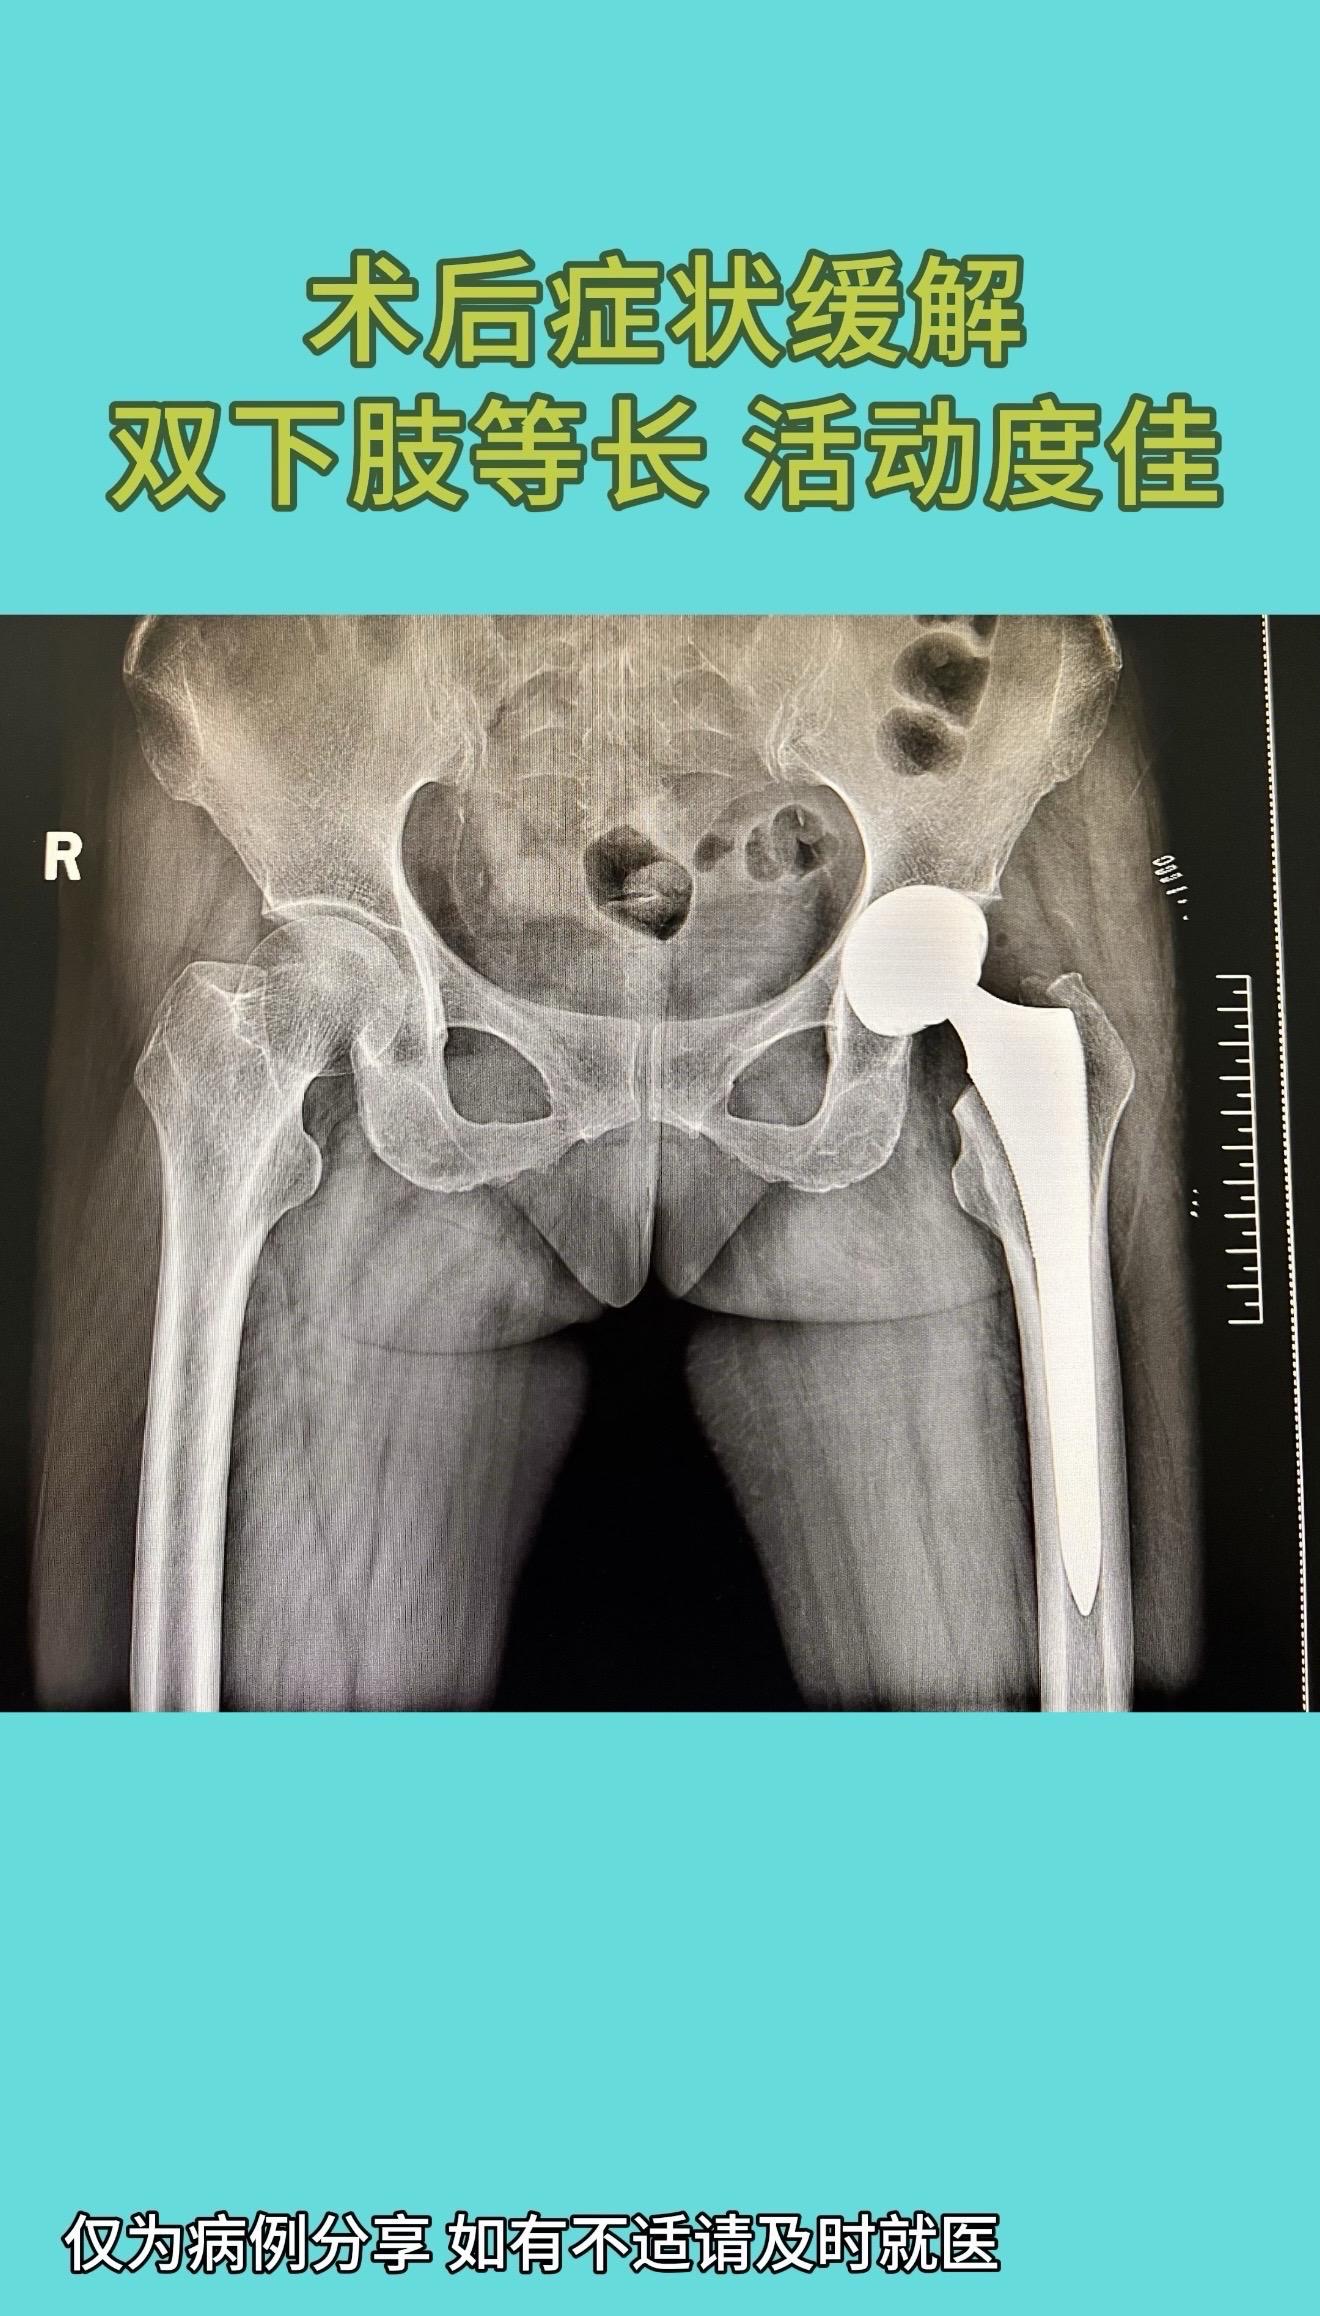

国内顶尖专家做的一例全髋置换手术:片子漂亮的像一件艺术品,术后症状缓解,双下肢等长,活动度佳。60多岁女性,股骨头坏死保守治疗半年,症状不断加重。